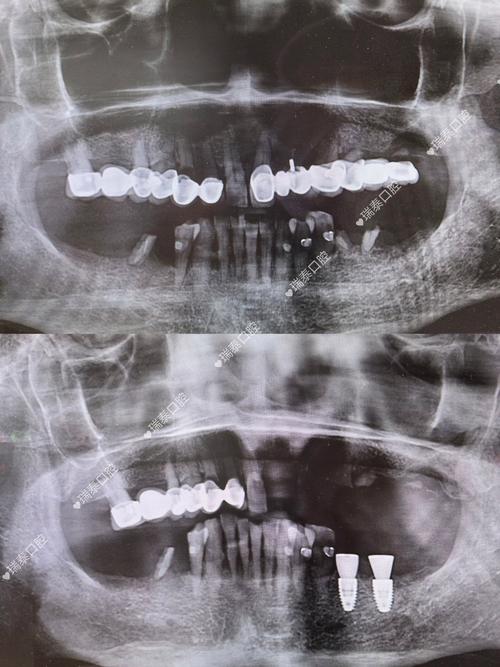

在临床使用流程中,愈合帽的安装通常在种植体植入术后即刻完成:医生会在种植体顶部预留内连接螺纹,将愈合帽旋入并施加适度扭矩,确保其与种植体紧密贴合且略高于牙龈平面(约1-2mm),既避免压迫牙龈导致缺血,又为牙龈生长提供引导空间,术后患者需特别注意口腔卫生,使用软毛牙刷、冲牙器或专用漱口水清洁愈合帽周围,避免食物残渣堆积;同时需避免用愈合帽侧咀嚼硬物、咬坚果或开瓶盖,防止其松动或移位,若愈合帽脱落或松动,需及时复诊,否则可能导致牙龈形态异常或种植体污染,影响后续修复效果,骨愈合期结束后,医生会拆除愈合帽,通过X光检查和临床评估确认骨结合状态良好后,再安装基台和取模制作牙冠,此时愈合帽的“过渡使命”即告完成。

需要注意的是,部分患者因牙槽骨条件较差(如骨量不足、骨质疏松),可能需要采用分期手术:先植入种植体并安装愈合帽,待骨愈合后再行二期手术切开牙龈,暴露愈合帽后拆除,再安装基台,这种情况下,愈合帽的保留时间会相应延长,患者需更严格遵循医嘱进行复诊和维护,确保牙龈和种植体处于健康状态。